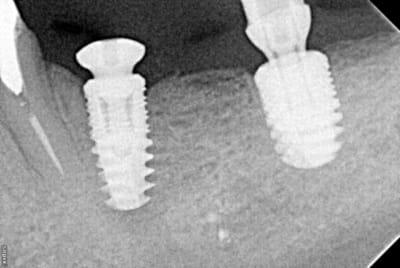

En illustration, j'ajoute des clichés pour RE expliquer pour ceux qu'on pas pigé que c'est opérateur dépendant.

cliché 1 : l'implant mésial a pas été assez enfoui, cratérisation distale (site d'extraction du jour de la pose)

cliché 2 : le pilier de droite est trop bas (pas de 3mm le jour de la pose, mais patient voulait une pro : mis un 1,5 angulé...bof). Sanction : ça commence à chier en mésial.

cliché 3 : enfouissement ok : quand c'est posé comme ça avec la bonne vis qui arrive à la bonne hauteur pour la prothèse définitive, on a JAMAIS de souci de "cratère"

cliché 4 : EII sur une 36, l'os a l'air de quand même bien aimer ce col quand la prothèse est à distance...

Moralité : c'est la prothèse qui dicte l'enfouissement, et pas le niveau osseux dispo. Mais ptêt que certains font autrement, après faut pas chercher pourquoi on cratérise : l'espace biologique.

NB : aussi faut pas le torquer comme un porc, c'est sûr, surtout en os dense...